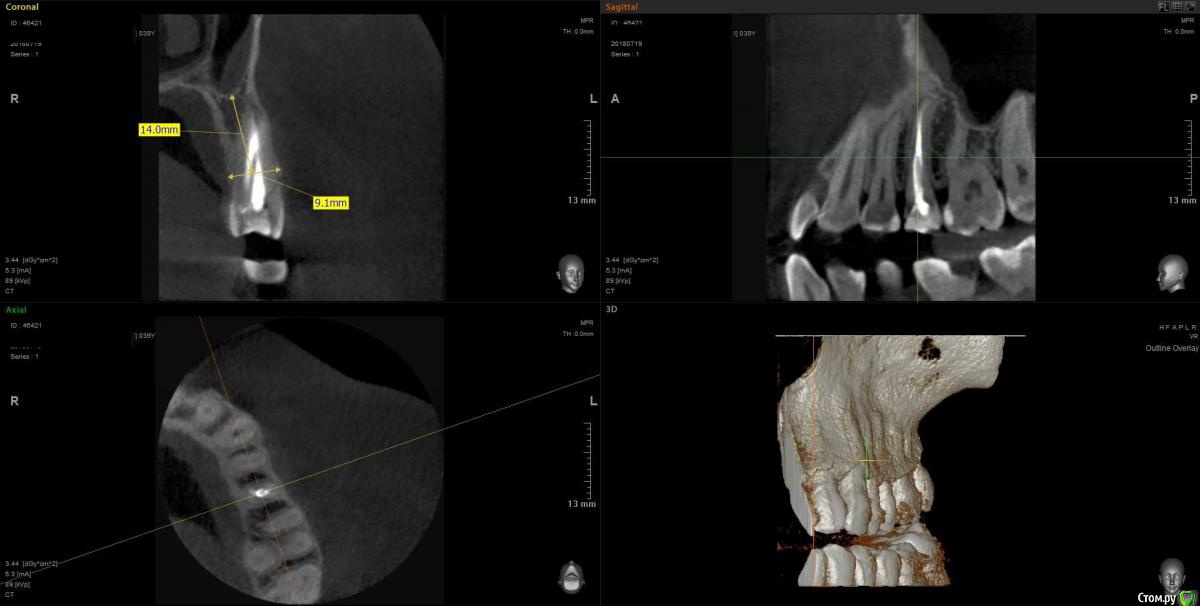

Eddie Опубликовано 21 июля, 2018 Поделиться Опубликовано 21 июля, 2018 (изменено) Добрый день, нуждаюсь в вашем совете. В клинике есть набор Nobel Tapered, которым, как я понял, можно установить Replace Select c полированной шейкой 0.75 мм и 1.5 мм, а так же груви. С нобелем раньше не работал, планируется одномоментная имплантация в позиции 25 зуба. Вопрос в том, как заглублять, работаю на осстем, в данном случае заглубил бы на 3-4 мм от зенита,а как с Nоbel-ем с полированной шейкой? Какой размер выбрать, выдержит 3.5? или лучше 4.3?( пациент крупный мужчина).Снимок прилагаю, причина удаления- продолный перелом Изменено 21 июля, 2018 пользователем Eddie Ссылка на комментарий

колесников Опубликовано 21 июля, 2018 Поделиться Опубликовано 21 июля, 2018 Все зависит от того как удалится зуб. Вероятно вестибулярная пластинка анкилозирована с корнем. Вы подумали о ваших дальнейших действиях если во время удаления получите дефект компактной пластинки до апекса? Я бы подумал над тактикой удаления,выбор импланта дело второстепенное. Однозначно надо будет заглубить 3-4мм, имплант застабилизируется только апексом,полированную шейку не желательно заглублять и вообще такой Имплант не подходит для одномоментный имплантации. Измерения предпочтительно производить не от внешних ориентиров гребня,а в пределах губчатой кости . Диаметр импланта для премоляра лучше выбирать измеряя мезиодистальный отрезок корня. 1 Ссылка на комментарий